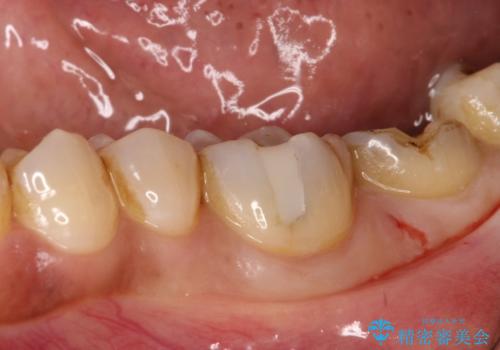

- 左下の奥歯の詰め物が取れたとのことで来院されました。診察したところ、左下6番には噛む力による複数のヒビ(クラック)が確認され、歯の寿命を考えると将来的な破折のリスクがある状態でした。

噛む力が強い方に多く見られる症状であり、これ以上の破折を防ぐためには補綴による補強が必要と判断しました。治療計画としては、左下6・7番ともに全体を覆うセラミッククラウンで補強し、咬合力に耐えられる状態に回復させる方針を立てました。また、清掃がしづらく炎症の原因にもなっていた親知らずについても、全体の予後を考えて抜歯することとしました。

まず左下6番のヒビや弱くなった部分を除去し、セラミッククラウンが適切に装着できる形に整えました。隣接する7番についても同様に支台形成を行い、両方の歯を連続して補強する形としました。クラウンは、見た目の自然さと耐久性を兼ね備えたセラミックを選択し、咬合圧に配慮したデザインと高さ調整を丁寧に行いました。